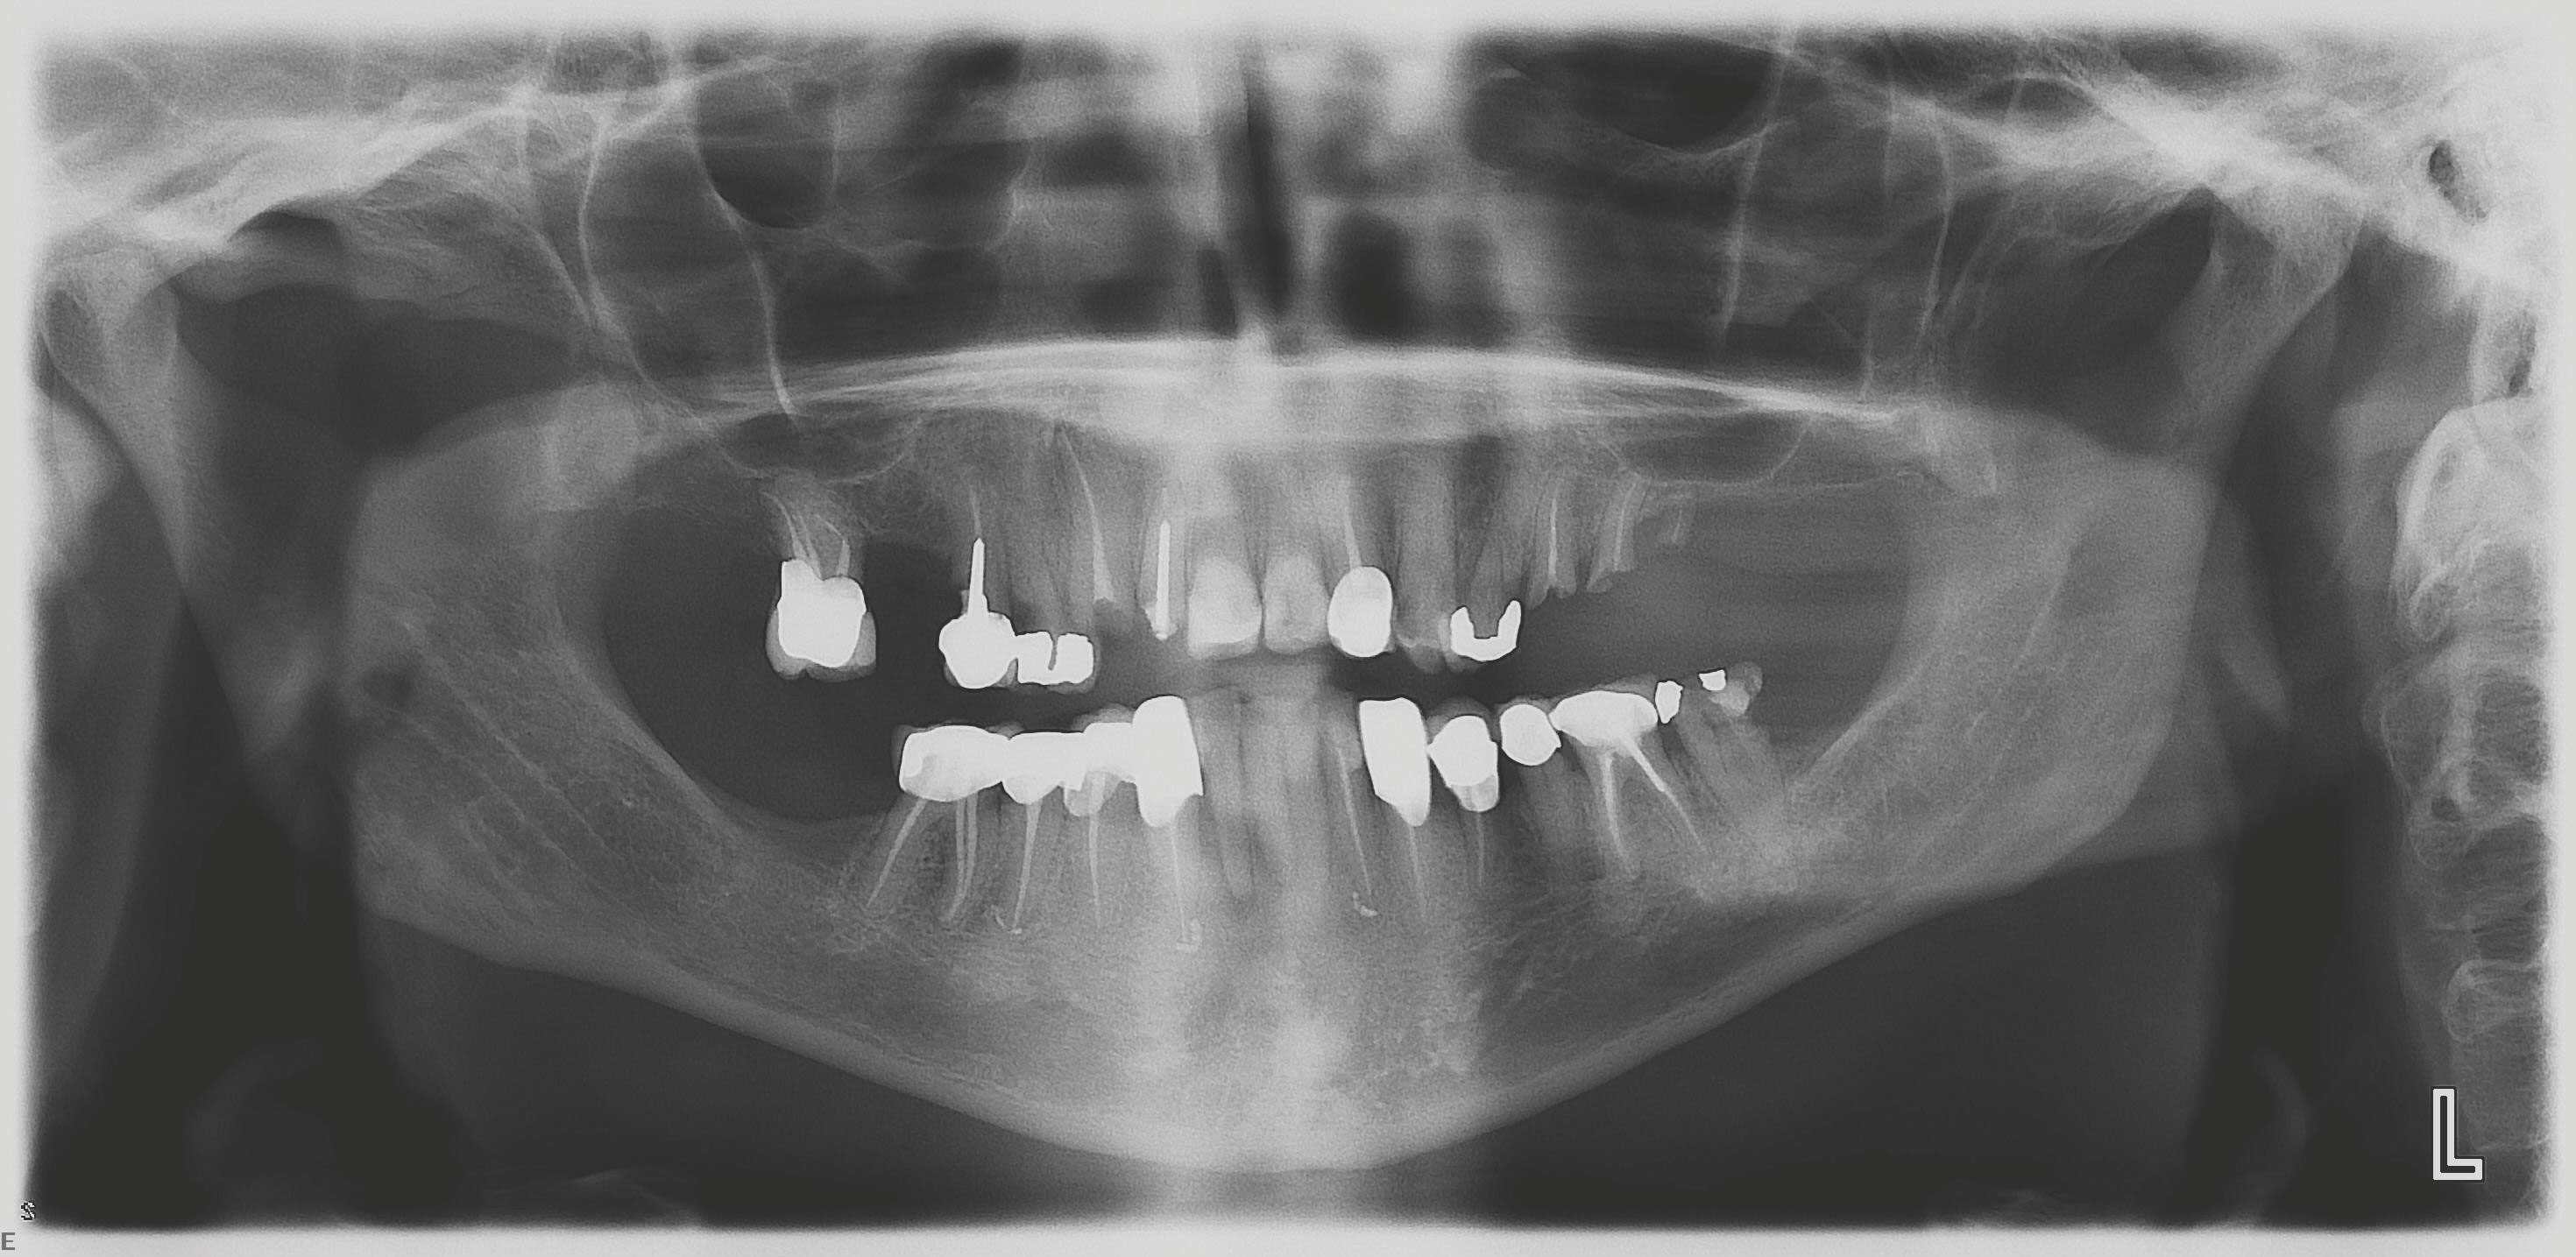

At the initial visit, a panoramic x-ray (Figure 11) and periapical x-rays were taken. The patient was photographed to capture her full face and shoulders, and a digital scan of the maxillary dentition was obtained. This file was electronically sent to the implant company to complete the VSD.

Fig 11. Initial panoramic radiograph.

Figure 11